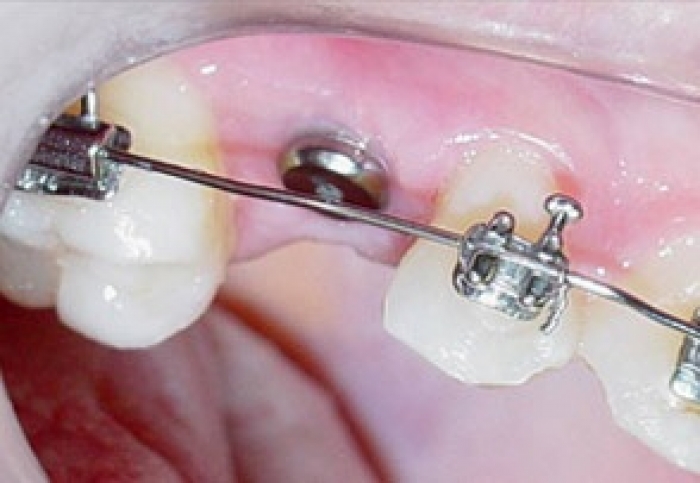

Imagem Inicial - Implante Instalado